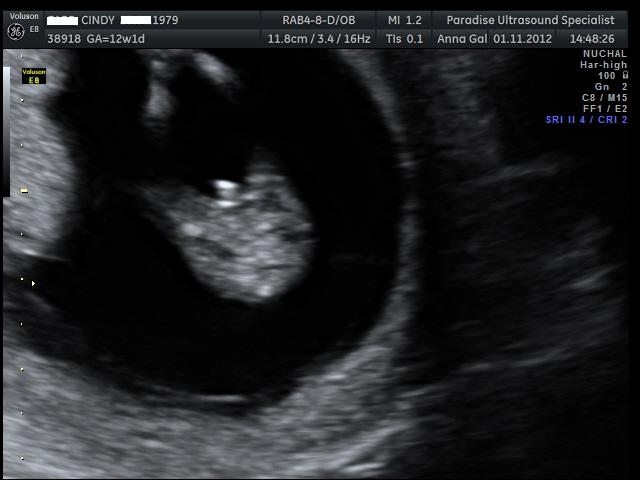

Here are the pics from my NT scan, the tech had a guess she said she is 70% positive the sex is.... can you guess? UPDATE - It's a boy :)